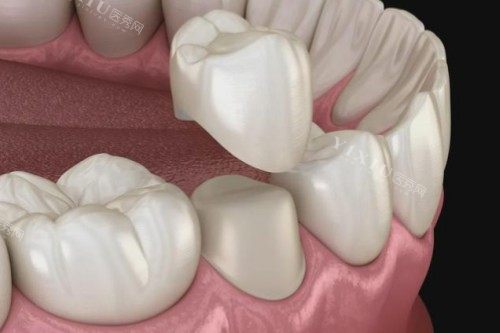

3. 全瓷牙:美学与功能的平衡

价格区间:880元-6800元/颗

代表产品:

国产经济型:武汉品德口腔的二氧化锆全瓷牙880元/颗

进口品质型:德派口腔的德国威兰德全瓷牙3600元/颗

奢望定制型:武大口腔的3M LAVA全瓷牙6800元/颗

适用人群:前牙美学修复、对金属过敏者。

优势:透光性强,牙龈无黑线;劣势:脆性较高,不适合后牙大范围缺损。

4. 烤瓷牙:传统修复的性价比方案

价格区间:380元-2500元/颗

代表材质:

普通金属:武汉品德口腔的钴铬合金烤瓷牙590元/颗

贵金属:纯钛烤瓷牙2500元/颗(生物相容性更佳)

超低价选项:部分机构促销价380元/颗(需确认材质靠谱性)

适用人群:后牙修复、预算敏感型用户。

优势:强度高,价格适中;劣势:长期使用可能导致牙龈染色。